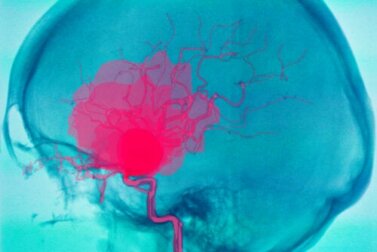

A hemorragia cerebral é uma situação grave que pode colocar em risco a vida de quem a sofre. Consiste em um sangramento no interior do cérebro que faz com que o sangue não seja distribuído e não atinja todas as partes do órgão adequadamente.

Uma hemorragia cerebral, como apontamos na introdução, é o sangramento que ocorre dentro do cérebro. Geralmente causa defeitos neurológicos de início súbito e até coma.

Isso ocorre devido à falta de suprimento de sangue para outras partes do cérebro, uma vez que o sangue não continua sua jornada através dos vasos sanguíneos. É importante distinguir entre hemorragia cerebral e hemorragia intracraniana.

As hemorragias intracranianas incluem, além da hemorragia cerebral, outras que ocorrem dentro do crânio, mas não no parênquima cerebral. Por exemplo, a hemorragia intraventricular, subaracnóide, subdural e epidural.